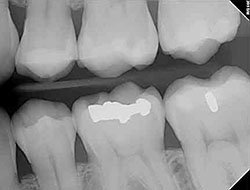

Using the most advanced dental technology possible is just as important as staying up-to-date on the latest treatment techniques. Because our practice is dedicated to providing you with the safest and most convenient treatment options available, we utilize advanced digital X-ray technology in our office.

Digital X-rays provide several advanced imaging options designed to save time, provide clearer dental photos, and expose patients to less radiation than with traditional X-ray technology.